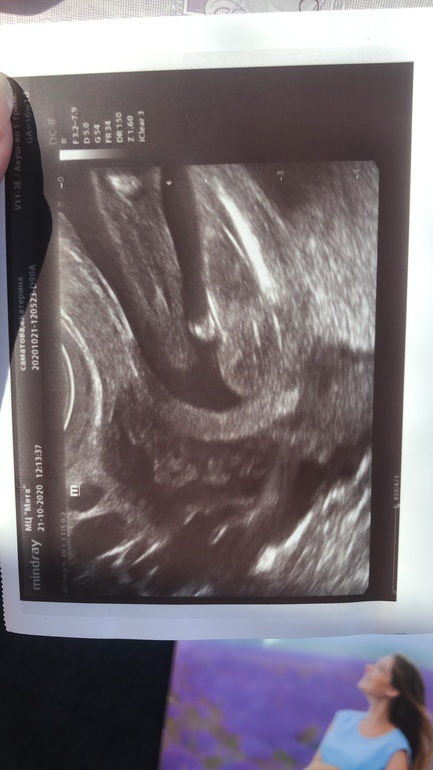

Похоже на девочку)Но вот половой бугорок удивил.Я думала он на таком сроке уже уходит.Нам в 16 недель сказали «ровная площадочка»,я конечно не знаю с какого ракурса она смотрела что так сказала.А фото снизу на 16+1 было таким)